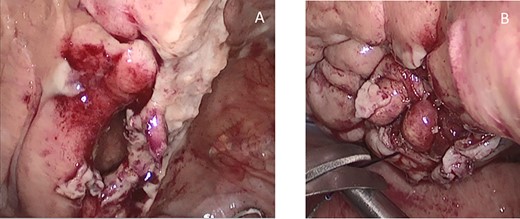

A supra-umbilical Hasson’s port was inserted and exploratory laparoscopy showed turbid effusion in Morrison’s pouch, spleno-renal pouch and pouch of Douglas. Two more trocars of 10 mm were inserted. Running the small bowel, a loop appeared densely adherent to the bladder and releasing the bowel from adhesions a bladder hole was found out (Fig. 3). The rupture of a bladder diverticulum was tamponade by an ileal loop and was critically inflaming the peritoneal cavity. An accurate laparoscopic adhesiolysis was performed. The ileal loops appeared vital and no bowel resection was necessary. The bladder hole was sutured with a knotless barbed suture. Dilute methylene blue was injected into the urinary catheter to check the watertight closure. No blue spreading was seen and a drain was inserted into pelvis. The surgery was performed by a skilled general surgeon and the consultant urologist wasn’t necessary.

Intraoperative findings of the bladder diverticulum, before (A) and after (B) suture.